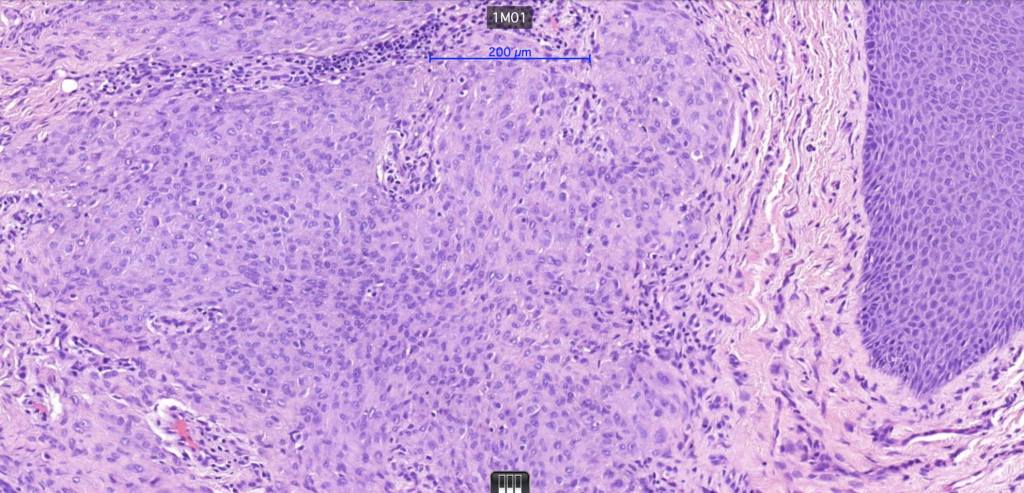

•Pure population of myoepithelial cells dispersed in sheet-like, reticular, whorled or fascicular patterns in a myxoid or hyaline stroma

•Cell types include epithelioid, spindled, histiocytoid & plasmacytoid

•No pleomorphism and absent or scanty mitoses

•Syncytial myoepithelioma characterized by sheet-like growth of ovoid to spindle cells with pale cytoplasm, syncytial borders & vesicular nuclei